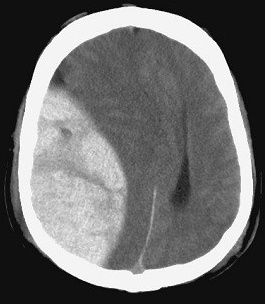

뇌 손상의 루시드 인터벌(lucid interval)

두개는 위의 그림처럼 겉에 두피가 있고 두개골이 있으며 그 아래에 비교적 두껍고 질긴 경막이 있다. 그 ...